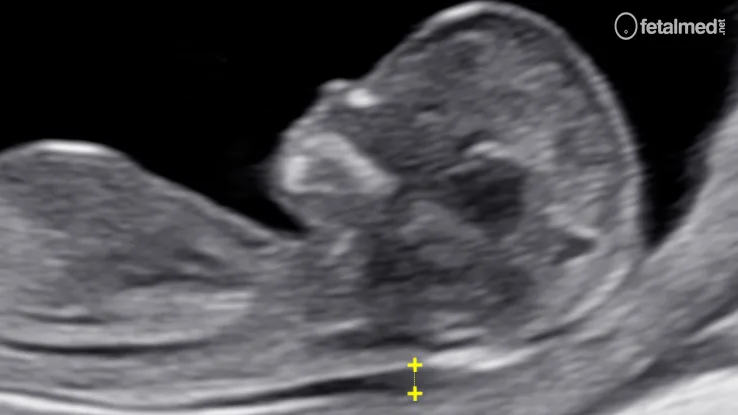

A translucência nucal (TN) é uma coleção de líquido na região da nuca do feto, visível ao ultrassom entre 11 e 14 semanas de gestação. Sua medida é um dos marcadores mais importantes no rastreamento de cromossomopatias, especialmente a síndrome de Down (trissomia do 21).